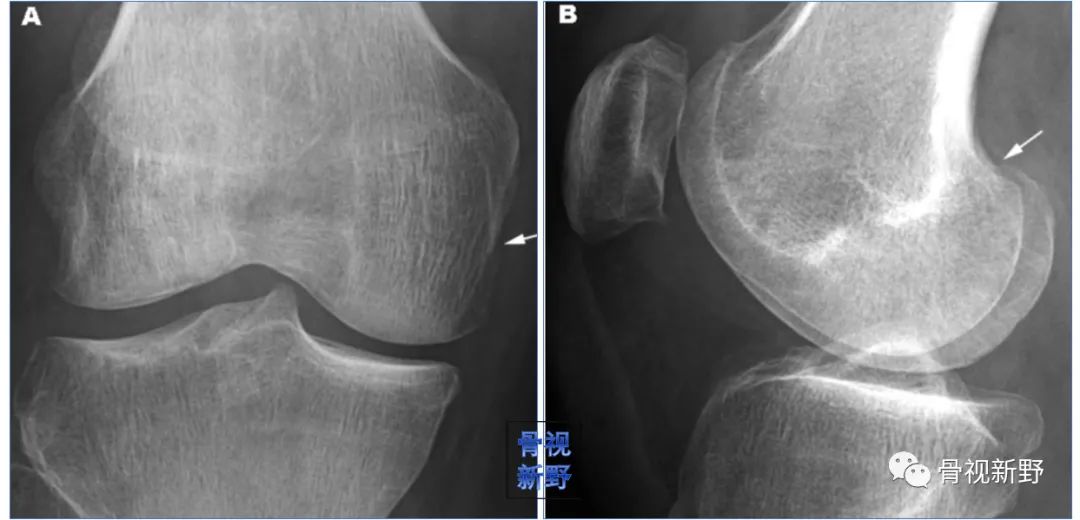

影像诊断:部分Hoffa骨折X线片不能提供明确的诊断,漏诊率较高。需要CT或MRI检查,并根据患者的病史、查体及影像学检查予以确诊。

部分Hoffa骨折普通X光片易漏诊